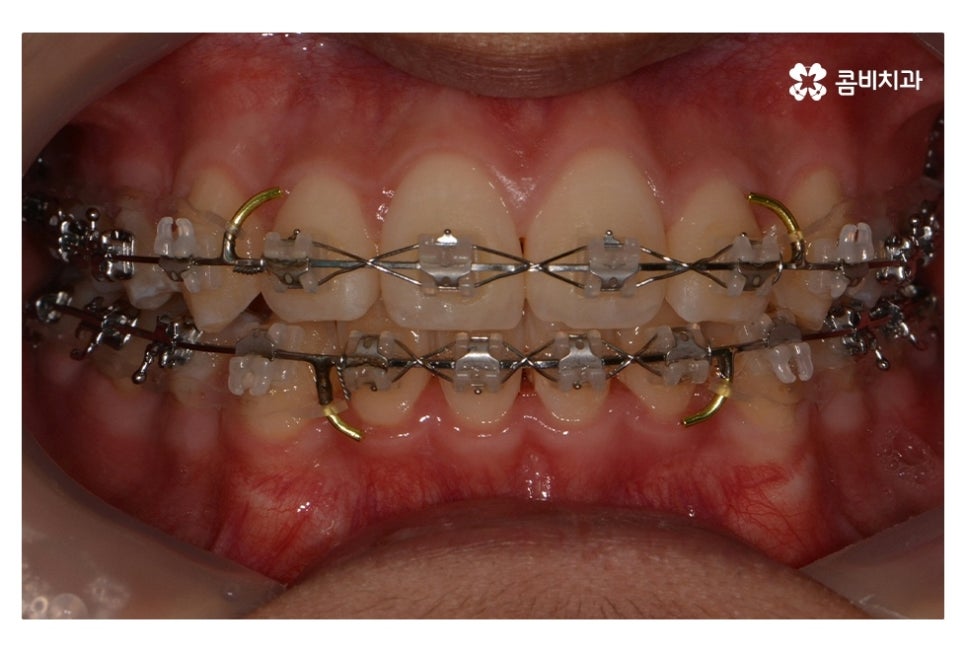

오늘 보여드릴 중학생치아교정 사례의 경우에는

악골의 위치는 정상적인 상태에서 불규칙한 치열로 인해

교정 치료를 진행한 사례라고 할 수 있어요.

위 환자분의 경우 발치가 진행된 사례로 치아의 이동 공간을

고려할 때 발치가 필요했고 환자분도 보다 나은

심미성을 위해서 동의한 상황이라고 할 수 있어요.

위 사진에서 보시면 시간이 지나면서 발치를 했던 치아의

공간이 사라지고 교정을 통해서 치열이 가지런해진 것을 확인할 수 있는데요.

중학생치아교정에 있어서 중요한 사항이 단지 치열만이

가지런해 보이는 것이 아닌 얼굴과의 조화와 교합이라 할 수 있어요.